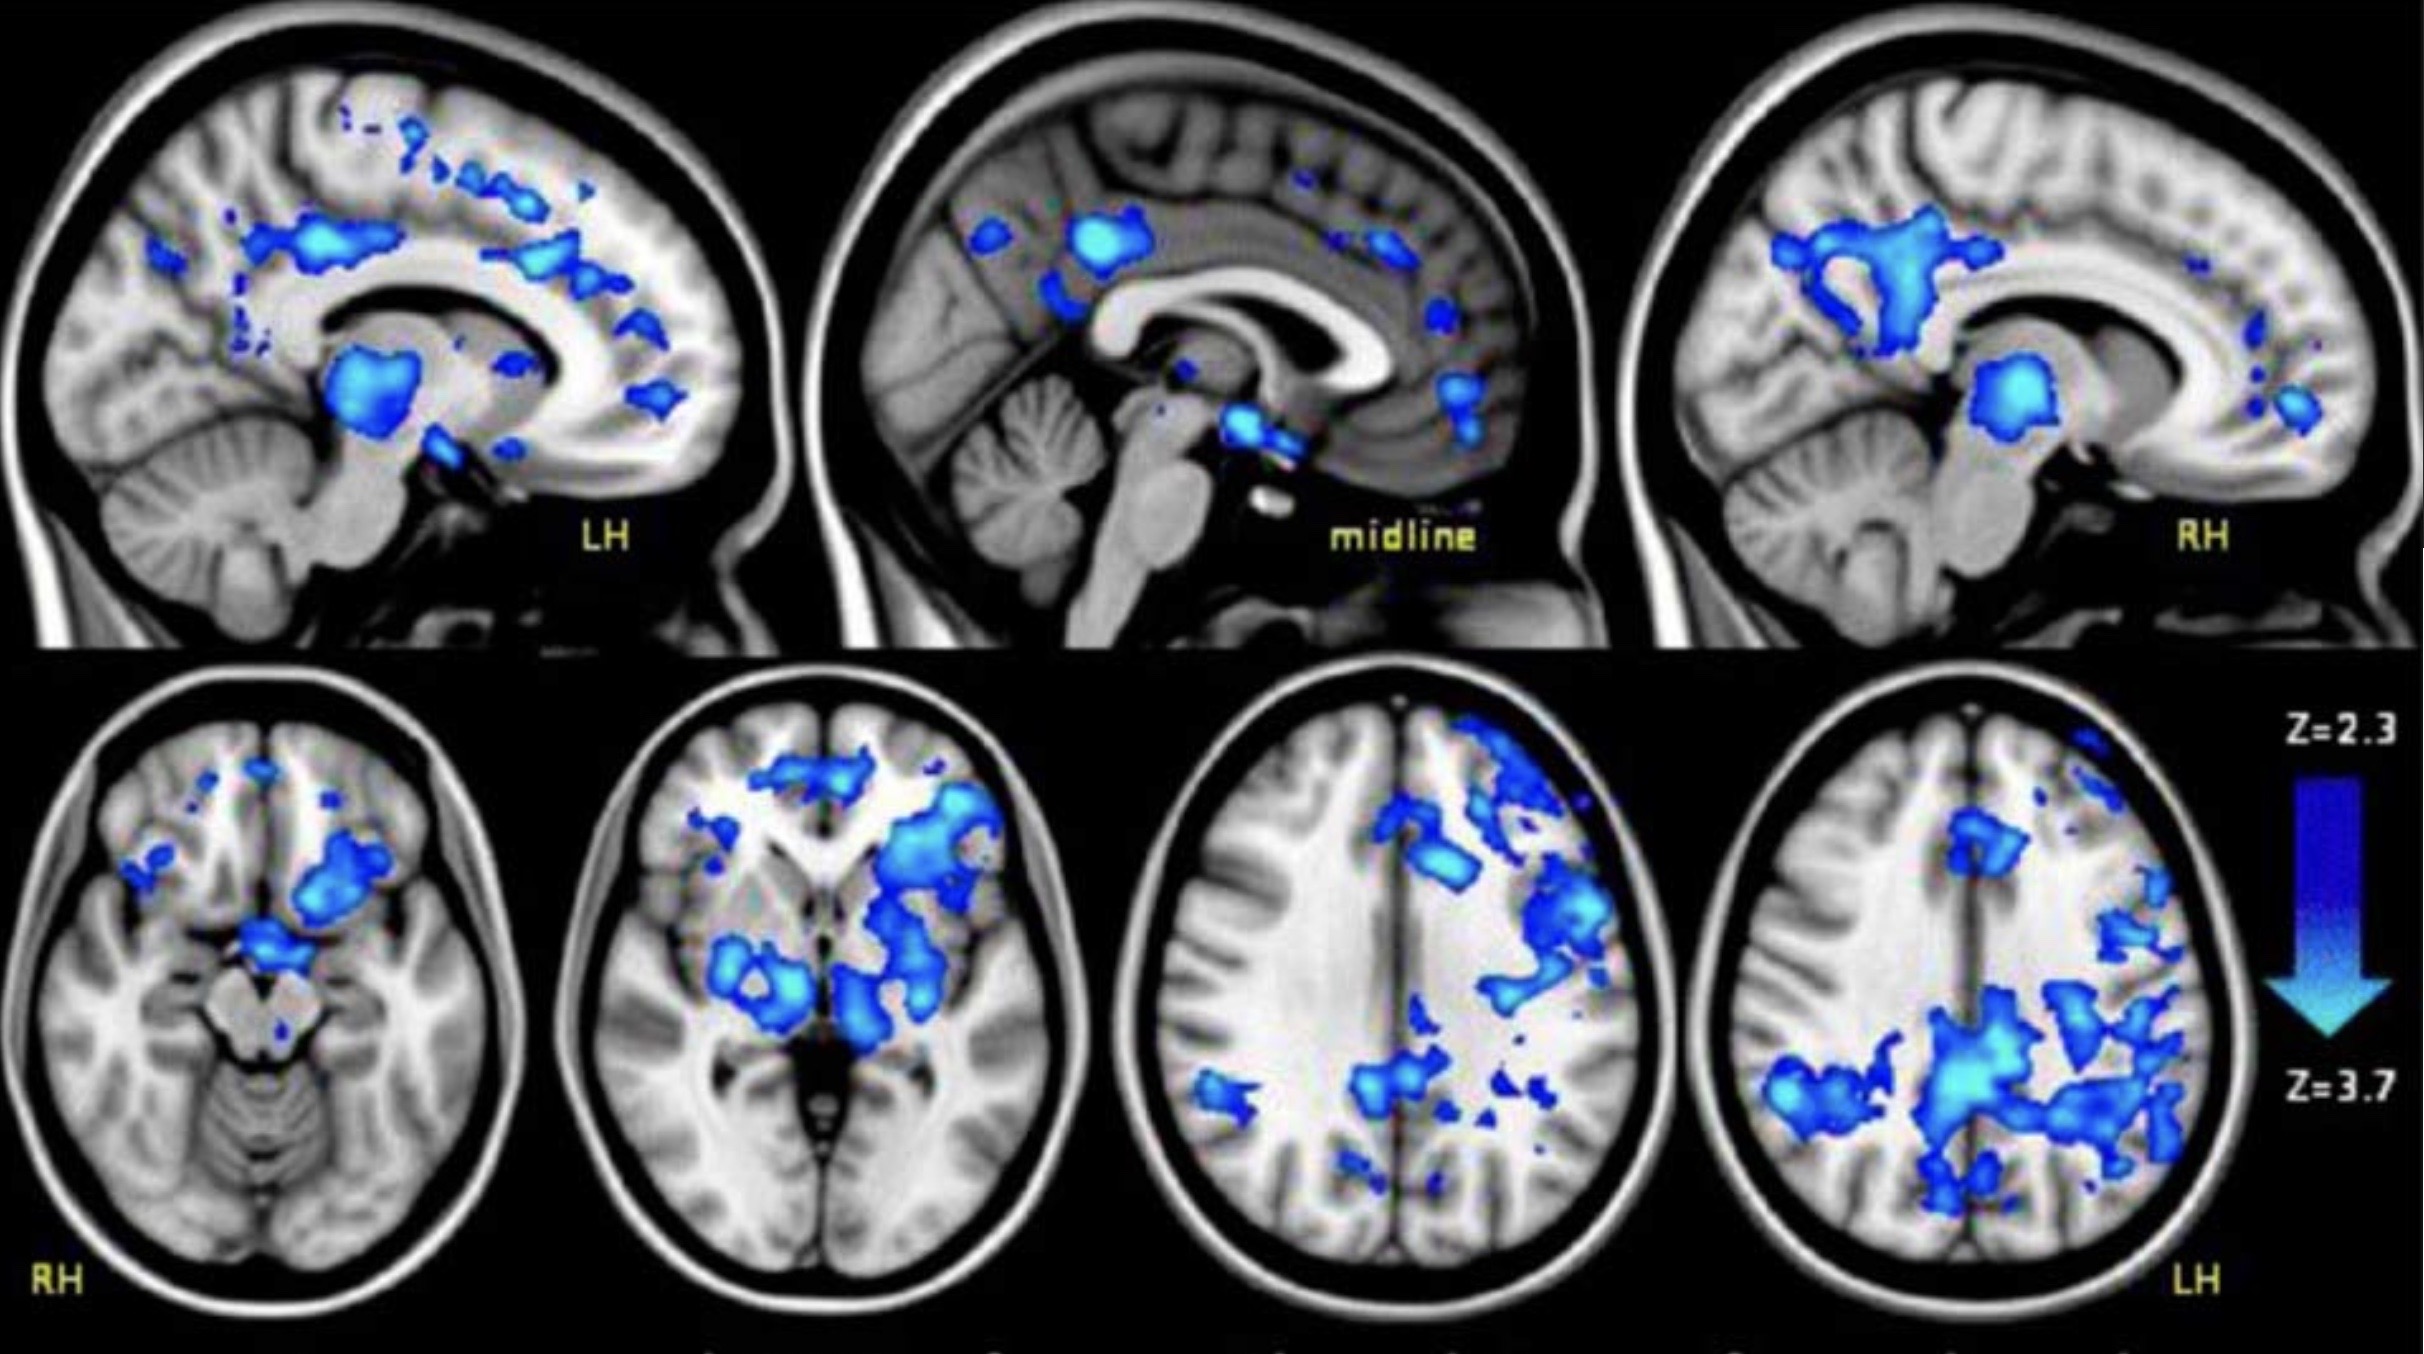

Despite the renewed interest in the benefits of psychedelics from popular figures such as environmentalist and author Michael Pollan, much of the research into these drugs was conducted in the 1950s and 60s with fairly rudimentary methods, Kwan said. In an effort to synthesize the disparate scientific information and bring it up to date, Kwan and a team of collaborators authored a review paper, “The Neural Basis of Psychedelic Action,” published Oct. 24 in Nature Neuroscience, that explains the basic neurobiology of how psychedelic drugs work at the chemical, molecular, neuronal and network levels, and raises topics for future exploration, such as the impact of compound psychedelics on different types of brain cells.

In research published last year in Neuron, Kwan used two-photon microscopy to show that a single dose of psilocybin increased the number of neuronal connections in a mouse brain by about 10%. That finding generated a number of follow-up questions – why are new neuronal connections being created, which pathways are strengthened and do these changes underlie psilocybin’s therapeutic effects? – which Kwan now plans to explore.